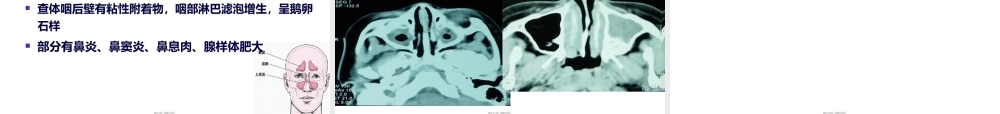

儿童慢性(mànxìng)咳嗽的诊断和治疗郑州大学第一附属(fùshǔ)医院儿科彭韶第一页,共四十五页。第一页,共四十五页。因咳嗽就诊者占呼吸专科门诊患者的因咳嗽就诊者占呼吸专科门诊患者的8080%以上%以上平均每个慢性咳嗽的病人看过平均每个慢性咳嗽的病人看过7.47.4个医师,平均每个病人做过个医师,平均每个病人做过8.58.5次检查次检查(jiǎnchá)(jiǎnchá)1999年,美、加和欧洲止咳药的费用高达7.5亿美元很多患者长期被误诊为“慢性支气管炎”或“支气管炎”大量使用抗菌药物治疗无效第二页,共四十五页。第二页,共四十五页。咳嗽持续4周以上依据(yījù)是急性呼吸道感染的病程大多持续10~25天2006年美国慢性咳嗽指南:≤14岁,咳嗽持续>4周。(Chest杂志2006年美国肺科医师协会出版)儿童咳嗽持续>4周。(中华儿科杂志08-46卷-2期,慢性咳嗽诊断与指南)第三页,共四十五页。第三页,共四十五页。咳嗽持续或反复>4周以上(yǐshàng)咳嗽为主要或唯一表现,伴随症状不明显肺部无体征胸部X线无异常相应处理治疗效果差第四页,共四十五页。第四页,共四十五页。咳嗽(késòu)咳嗽(késòu)中枢效应器官受体呼吸肌声带腹膈肌传出支脊髓运动神经迷走神经膈神经喉返神经脑干上部桥脑传入支迷走神经三叉神经舌咽神经咽喉至终末支气管鼻、鼻窦、耳鼓膜、胃、心包、膈肌第五页,共四十五页。第五页,共四十五页。生理意义阻止异物(yìwù)、病原体等进入下气道清除已进入气道的异物、过多分泌物清除呼吸道刺激因子防止感染扩散第六页,共四十五页。第六页,共四十五页。病理状态下的并发症胸内压升高40KPa(300mmHg)呼出气体速率28米/秒自发性气胸和出血肺感染(gǎnrǎn)扩散、肺不张、肺气肿心力衰竭、心律失常头痛、晕厥骨折、伤口破裂、疝出现、尿失禁流行病学疾病传播第七页,共四十五页。第七页,共四十五页。呼吸道感染变态反应性疾病异物或其他刺激呼吸道受压先天气(tiānqì)道畸形心血管系统神经精神因素其他第八页,共四十五页。第八页,共四十五页。其他:~~EB~~AC~~结核~~感冒后咳嗽~~支气管扩张~~心理性咳嗽小儿成人老年人CVA322418PNDS234148GERC152120第九页,共四十五页。第九页,共四十五页。常见病因感冒后咳嗽(感染后咳嗽)咳嗽变异性哮喘上气道咳嗽综合征(PNDs)胃食管返流嗜酸粒细胞性支气管炎腺样体肥大、慢性扁桃体炎慢...